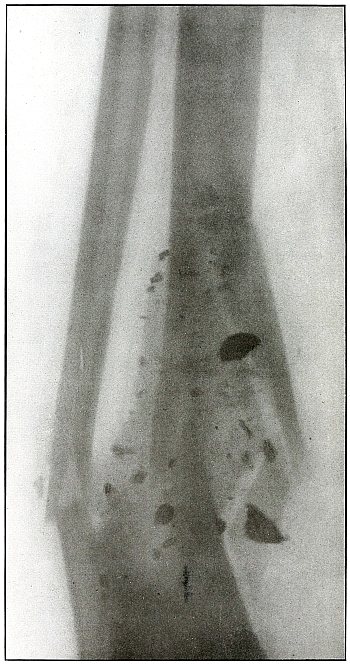

Gunshot wound, multiple, leg |

308 |

| 150. |

Gunshot fracture, astragalus |